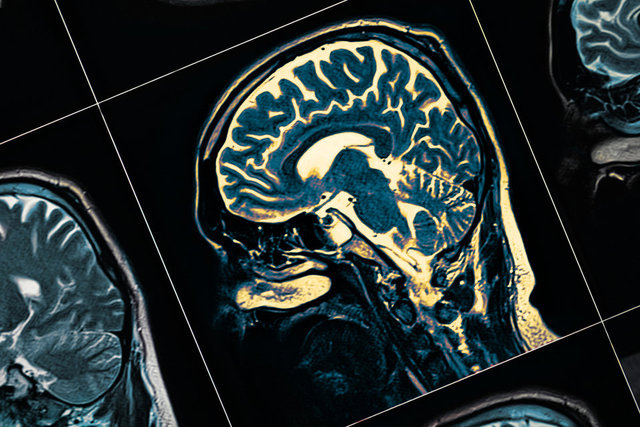

ALZHEİMER TEDAVİSİ

Özellikle belli bir yaştan sonra ortaya çıkan unutkanlık hastalığı Alzheimer için Eisai ve Boigen şirketleri tarafından geliştirilen ilacın deney sonuçları, eğer erken teşhis edilir ve uygulanırsa, hastalığın ilerlemesini yavaşlattığını gösterdi.

Deneyin detaylı sonuçları henüz yayımlanmadı ancak paylaşılan kısıtlı veriler bile Alzheimer hastalığına umut oldu.

İlacın adı Lecanemab, hastalığa yakalanan kişilerin beyninde biriken toksik beta- amiloid proteinlerini ortadan kaldırmayı başarıyor.

Bilim insanları uygulanan bu ilacın "tarihi bir gelişme" olduğunu belirtti.